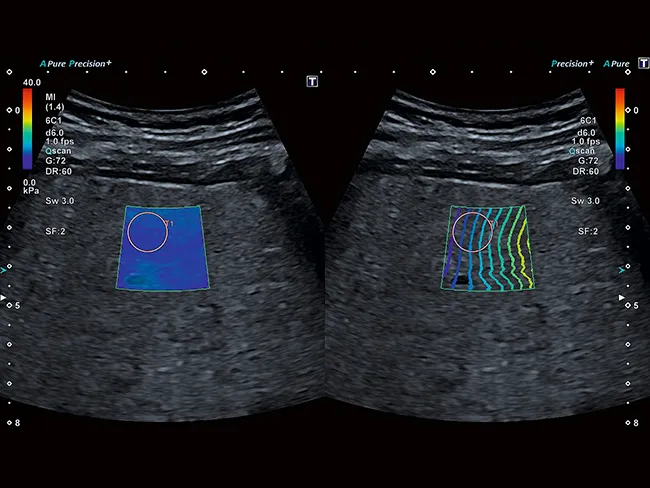

Технология сдвиговых волн Aplio обеспечивает количественное измерение эластичности тканей и отображение ее в режиме реального времени в различных клинических условиях. Интеллектуальные карты помогают визуально оценить распространение и качество эластограммы.